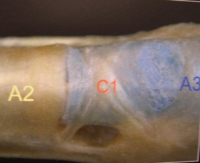

2/ la poulie A2, 17 mm, est la plus importante d'un point de vue fonctionnel et dynamique. Elle est aussi la plus longue. Elle s'insère sur les 2/3 proximaux de la première phalange. Lors de la flexion, elle empêche les tendons fléchisseurs de s'écarter de la corticale antérieure phalangienne et de "prendre la corde de l'arc".

3/ la poulie A3, 3 mm, est de petite taille. Elle est située en regard de l'articulation inter-phalangienne proximale, amarrée à la plaque palmaire.

Elles sont au nombre de 3. C1, C2, C3 sont situées respectivement entre A2 et A3, entre A3 et A4 et entre A4 et A5.